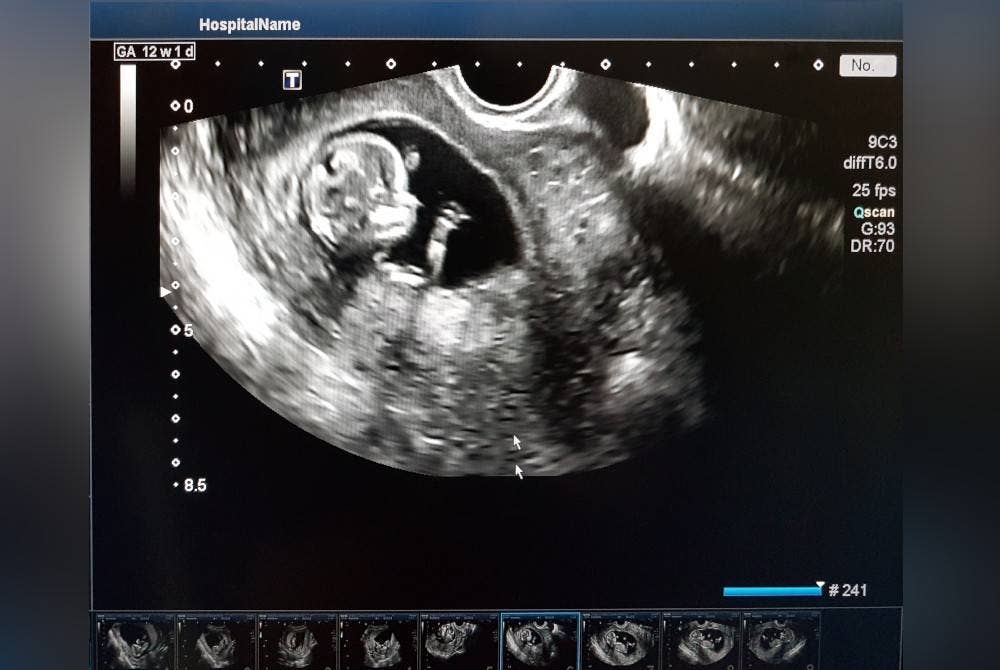

Mesin imbas bayi di klinik kerajaan uzur, ketinggalan zaman

Tidak disangka, mesin pengimbas di klinik swasta berjaya mengesan denyutan bayi dan disahkan telah mengandung dua bulan. Kini bayi perempuan yang comel itu juga selamat dilahirkan.

Mereka masing-masing berkongsi kisah di ruangan komen video berkenaan dengan mendakwa mesin pengimbas kandungan di klinik kesihatan sudah uzur dan ketinggalan zaman.

Jika tersilap jantina bayi, ia bukan perkara serius namun kesilapan menentukan status nyawa kandungan menerusi kadar denyutan nadi, ia tidak boleh dipandang remeh.

Mesin pengimbas sangat penting bagi melihat perkembangan bayi selain mengesan komplikasi awal, penyakit dan kecacatan.

Jika mesin pengimbas berkualiti, ia dapat mengelak sebarang kesilapan tafsiran mengenai pertumbuhan bayi.